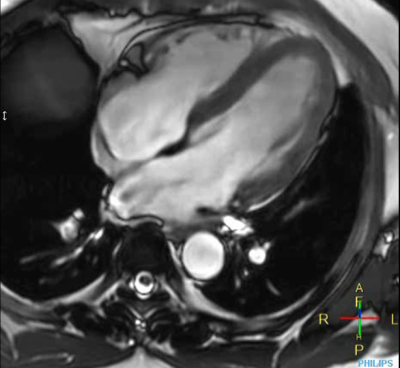

Cine 2D BFFE (4 CAV)

Elition X 3.0T

東京警察病院